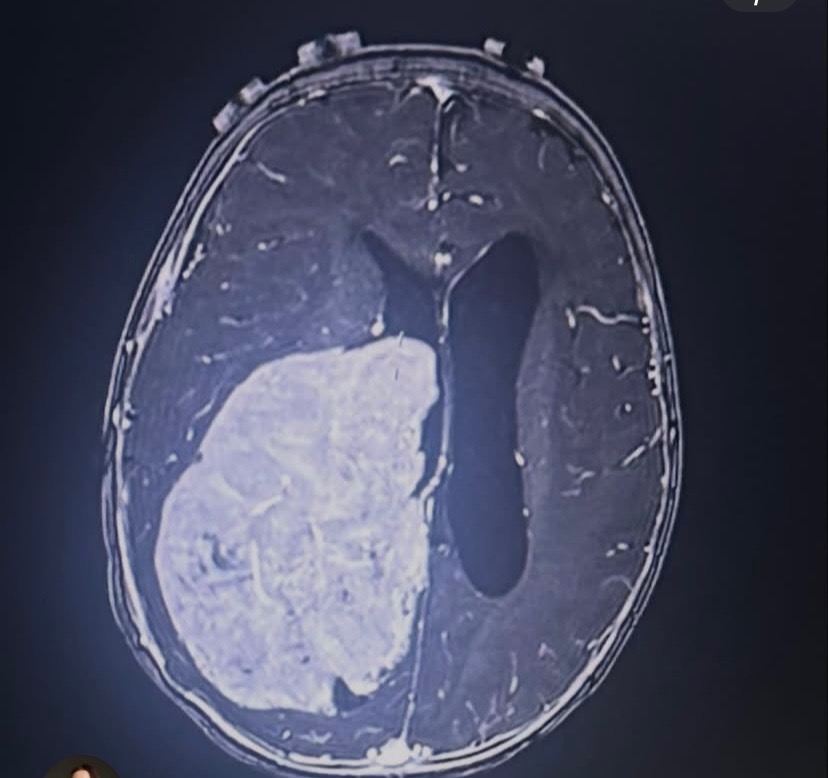

Amber and Collin’s precious baby boy, Courtland, has been in and out of the ER and is now in the PICU after doctors discovered a large brain tumor covering a significant portion of his brain. Their world changed in an instant.

This journey has already been incredibly difficult. During surgery, doctors were only able to remove about 20% of the tumor before complications arose. Courtland’s tiny body began to struggle — his blood pressure dropped, and his heart stopped for 30 minutes.

In the midst of fear and uncertainty, God showed His mercy — an MRI after surgery revealed no brain damage. That alone is nothing short of a miracle.

Courtland remains in the PICU under constant monitoring. He has experienced additional complications, including a seizure, inflammation at the surgical site, and fluid buildup in his brain. Doctors are now planning to place a shunt to help relieve that pressure. He has been hospitalized since early February, and the road ahead is still long and uncertain as they continue treating his diagnosis of choroid plexus carcinoma. They are working to get him stong enough to begin Chemo. Which will transfer him to oncology